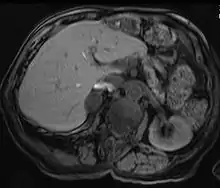

Adrenal adenomas are common, and are often found on the abdomen, usually not as the focus of investigation; they are usually incidental findings. About one in 10,000 is malignant. Thus, a biopsy is rarely called for, especially if the lesion is homogeneous and smaller than 3 centimeters. Follow-up images in three to six months can confirm the stability of the growth.

While some adrenal adenomas do not secrete hormones at all, often some secrete cortisol, causing Cushing's syndrome, aldosterone causing Conn's syndrome, or androgens causing hyperandrogenism.